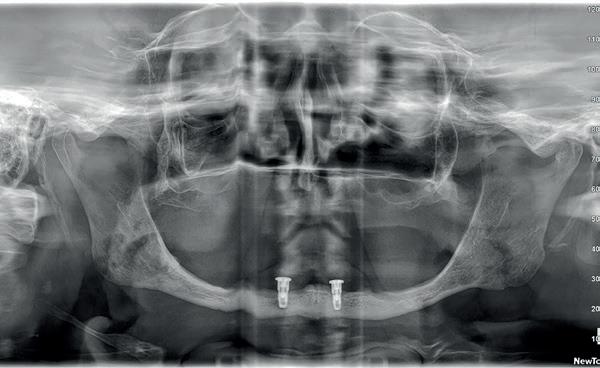

Tweede fase chirurgie

Na de genezingsperiode werd eerst een OPT röntgenopname vervaardigd om de genezing van de implantaten, kaakverbreding en sinusbodemelevatie te beoordelen. Er waren geen complicaties opgetreden. Bij de tweede fase chirurgie is het van absoluut belang dat er minimaal 2-3 mm gekeratiniseerd weefsel aan de buccale zijde van de implantaten wordt verkregen, anders kan de patiënt de implantaten niet goed reinigen en door de trekkrachten van de mucosa ontstaat al gauw peri-implantaire ontstekingen en recessies. De incisie hoeft niet van tuber tot tuber te zijn, maar 2 incisies van de 16 tot de 12 en 26 tot de 22 is voldoende, waarbij de incisie genoeg gekeratiniseerd weefsel aan de buccale zijde bevat, dat naar

de buccale zijde van de implantaten wordt geduwd. Er werden 6 healing abutments van 6 mm hoogte op de implantaten geplaatst, waarna de wonden werden gehecht met een 6-0 monofilament hechtdraad. In de prothese werd een nieuwe softliner over de healing abutments geplaatst. Het weefsel dient minimaal 4 weken genezingstijd te hebben (afbeelding 6).

22. Controle OPT na 2 jaar